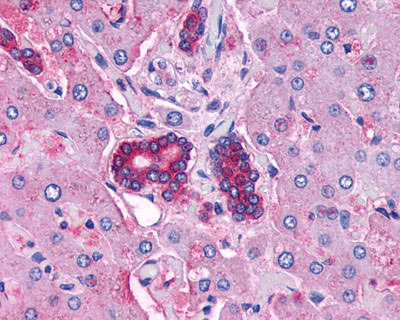

Anti-VPAC2 / VIPR2 antibody IHC of human Pancreas, Carcinoma.

Anti-VPAC2 / VIPR2 antibody IHC of human Breast, Carcinoma.

Anti-VIPR2 antibody APR01962G IHC of human liver and bile ducts. |